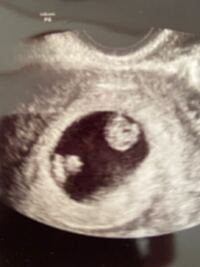

双子だとわかるのはいつ? 病院の検査で双子だとわかるのは 早くて妊娠5週の後半 です! 二卵性の双子の場合は、はじめての受診でわかることがほとんどです! 妊娠を確認するための超音波(エコー)検査で、胎嚢が二つ確認できれば双子だと確定され 無脳症はいつわかる? 先天異常とは、赤ちゃんが生まれつき持っている異常のことです。 ここでは、そんな 先天異常のなかでも、無脳症についてご紹介します。 無脳症とは具体的にどんな異常なのか、妊娠したらどの時期からわかるようになるのか妊娠5週目~7週目でわかる人が半数! 双子妊娠がわかった時の週数も尋ねたところ、 5週目~7週目でわかる人が半数 でした。

双子の妊娠っていつ分かるの? それではいよいよ、双子の妊娠がいつ分かるのか?という事について説明します。結論から言いますと、双子の妊娠は 早い人なら妊娠5週ぐらいで分かります。 半数以上の妊婦の方が、初回の妊婦検診で妊娠が分かっています 双子妊娠発覚! いつわかる? リスクは? まとめ 突然の双子や三つ子ちゃんの判明で動揺された方が多いと思います。 育児は確かに想像通り大変ですが、 やっぱり赤ちゃんが並んでいるところや遊んでるところを見ると癒されるし、可愛さも2倍以上 双子の妊娠発覚はどのタイミングでわかるの? 私の場合は、妊娠5週目で『胎嚢 (たいのう)=赤ちゃんのベッドのようなもの』を見つけました。 1回目の検診では、1つの胎嚢の確認で単胎児